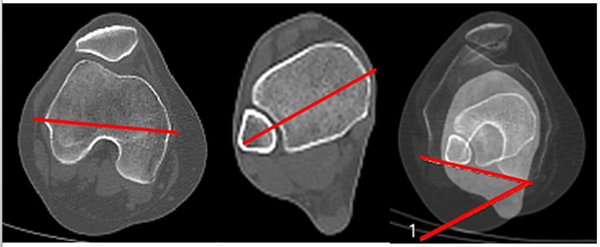

Lateralización del TAT

Esta medición se realiza en extensión completa de rodillas. Es una proporción determinada a partir de dos imágenes de la epífisis proximal de la tibia.

Una de ellas es donde se visualiza el platillo tibial en su mayor diámetro transversal con otra imagen donde se visualiza la inserción del tendón rotuliano en el tubérculo tibial anterior. Ya superpuestas estas imágenes, trazaremos una línea basal que pasará por el borde posterior de la meseta tibial. A partir de ahí, mediante líneas perpendiculares, determinaremos dos distancias que representarán el diámetro transversal mayor de la epífisis proximal de la tibia entre los bordes medial (punto A) y lateral (punto B): distancia A-B.

La otra distancia será la comprendida entre el centro de inserción el tendón rotuliano en el tubérculo tibial anterior (punto C) y el borde medial del platillo tibial (punto A): distancia A-C. La lateralización del TAT se calcula como un porcentaje del ancho de la tibia: A-C / A-B x 100. Ando encontró 64% ± 6% en grupo control y 79% ± 9% en grupo con inestabilidad.13 Prakash encontró 60.7% ± 3.1 en grupo control versus 64.1% ± 2.8 en grupo con inestabilidad14 (fig. 10).

Figura 10: Lateralización de tuberosidad tibial. Se calcula mediante la superposición de dos cortes, uno donde se visualiza la parte más ancha de tibia proximal, y otro corte donde se visualiza la inserción del tendón patelar en TAT. Se marcan tres líneas perpendiculares a la cortical posterior de tibia superior. A) Pasa por cortical medial. B) Pasa por cortical lateral de tibia. C) Pasa por el centro de inserción del tendón patelar. La lateralización se calcula: A-C/A-BX x 100. Se estima el porcentaje de la lateralización.

Medialización del surco

Esta medición también se realiza en extensión completa de rodillas, en el corte axial de la epífisis distal del fémur que represente la mayor profundidad del surco troclear.

Se traza la línea bicondílea. A partir de esta y mediante perpendiculares se determinarán dos distancias en sentido transversal. La primera es la distancia entre el epicóndilo medial (punto A) y el lateral (punto B), la segunda distancia se mide desde la mayor profundidad del surco troclear (punto C), hasta el borde del epicóndilo medial. La medialización del surco es el porcentaje que la distancia A-C ocupa del segmento A-B. Ando, en su estudio, halló 49% ± 5% en grupo control, y 46% ± 6% en grupo con inestabilidad13 (fig. 11).

Figura 11: Medialización de surco. Corte tomográfico a nivel del fémur distal donde se visualiza signo de arco romano. Se trazan tres líneas perpendiculares a la línea bicondílea. A) Pasa por el borde medial de ancho de cóndilos femorales. B) Perpendicular que pasa por el borde lateral de cóndilos femorales. C) Perpendicular que pasa por el punto más profundo del surco de tróclea femoral. Porcentaje de medialización del surco se calcula: A-C/A-B x 100.

Rotación de la rodilla (femorotibial)

Esta medición se realiza en extensión de rodilla. La rotación de la rodilla se determina al superponer dos imágenes: el corte de línea bicondílea, donde se visualiza el platillo tibial en su mayor diámetro transversal. Se traza la línea bicondílea y otra que delimita el borde posterior de la tibia proximal. El ángulo formado por la intersección de las líneas corresponde con la rotación de la rodilla femorotibial. Valor normal de 3.2°.9, 15 Es importante diferenciar esta “rotación” del fémur en relación con la tibia, de la “torsión de la rodilla en su conjunto” en relación con el miembro y la dirección de avance del cuerpo a la cual denominamos “torsión de rodilla” (fig. 12).

Figura 12: Rotación femorotibial. Se mide luego de la superposición de dos cortes de cóndilos femorales donde se visualiza el arco romano, y corte de tibia proximal donde se ve máximo el ancho. Ángulo con la intersección de línea bicondílea y línea paralela al borde cortical posterior tibial. Normal: de 3 a 5°.